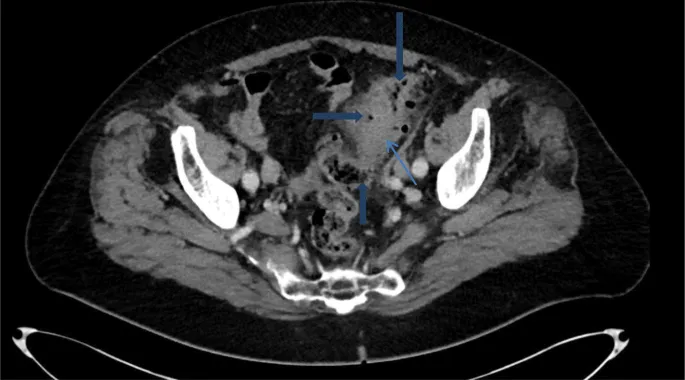

- Imaging: Abdominal/Pelvic CT with contrast is the gold standard.

- Key CT Findings: Sigmoid wall thickening (>4 mm), pericolic fat stranding, abscess, fistula.